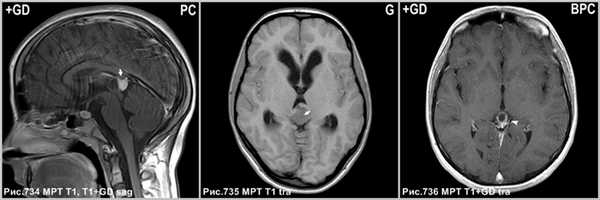

Дифференциальный диагноз

Герминома

Герминома - злокачественная, чаще солидная опухоль с петрификатом в центре, в то время как пинеоцитома обызвествляется по периферии. Герминома метастазирует и инфильтрирует таламусы.

Пинеобластома

Пинеобластома - первично злокачественная опухоль (как медуллобластома, ретинобластома или эпендимобластома, прежде входила в состав ПНЭО). Опухоль плохо отграничена, имеет инвазивный характер роста. Возникает в возрасте до 20 лет. Содержит кисты и некрозы, обычно крупная на момент первого исследования и осложненная гидроцефалией. Всегда имеются метастазы.

Киста шишковидной железы

Постконтрастное Т1 демонстрирует накопление агента в солидном участке опухоли (стрелки на рис.734). В центре герминомы определяется петрификат (стрелка на рис.735) и отсутствующее обызвествление по периферии. Накопление контраста в стенке кисты шишковидной железы (головка стрелки на рис.736).